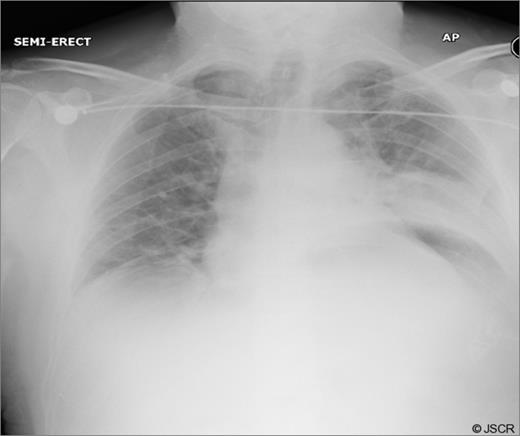

During the sac dissection, the patient developed tension pneumothorax due to an iatrogenic tear of the right pleura requiring a chest drain. He was closely observed in the high dependency unit with pain relief through PCA (morphine) and intravenous paracetamol and oral feeding commenced post-operatively. Arterial blood gas showed pO2 of 10.7 and PCO2 of 6.54 on 60% oxygen and an early post-operative chest x-ray revealed bilateral pulmonary infiltration (Fig. 3). Non-cardiogenic pulmonary oedema was suspected and the patient was started on 5mmHg pressure CPAP.

Early post-op chest x-ray showing patchy shadowing/ consolidation over the left side of chest